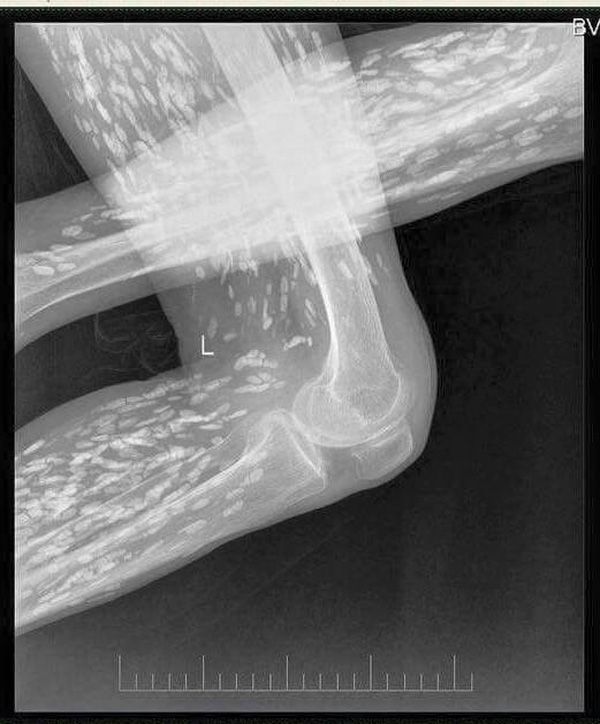

Theo hình ảnh chụp bằng X-quang được cung cấp trên mạng xã hội, nạn nhân đã bị nhiễm sán sơ mít ở giai đoạn vôi hóa. BS Lương Quốc Chính (Bệnh viện Bạch Mai) chia sẻ trên facebook cá nhân: “Rất nhiều người vẫn cho rằng đây không phải là hình ảnh của nhiễm sán vì không thể có chuyện sán lại cản quang trên phim X-quang được, nhưng vì đây là tổn thương đã vôi hóa nên mới cản quang như vậy, chỉ cần sử dụng hai từ khóa Cysticercosis, Trichinellosis để search tìm ảnh trên google sẽ thấy những hình ảnh tương tự”.

Thông tin “người gạo” đang được cư dân mạng chia sẻ rầm rộ trên mạng xã hội. (Ảnh: BS Luong Quoc Chinh)

Đối với bệnh nhân đã ở giai đoạn “người gạo”, bệnh nhân nhiễm ấu trùng sán lợn kén vôi hóa thường xuất hiện dạng nốt nhỏ trên phim ở vùng lưu hoành. Các tổn thương này đã từng được coi là không gây triệu chứng lâm sàng, nhưng gần đây đã có nhiều bằng chứng cho thấy chúng là căn nguyên gây co giật và các triệu chứng thần kinh khu trú. Phù quanh tổn thương ở bệnh nhân “người gạo” có thể biểu hiện bằng các triệu chứng nặng như co giật và liệt khu trú, nhưng cũng có thể không biểu hiện gì đặc biệt.